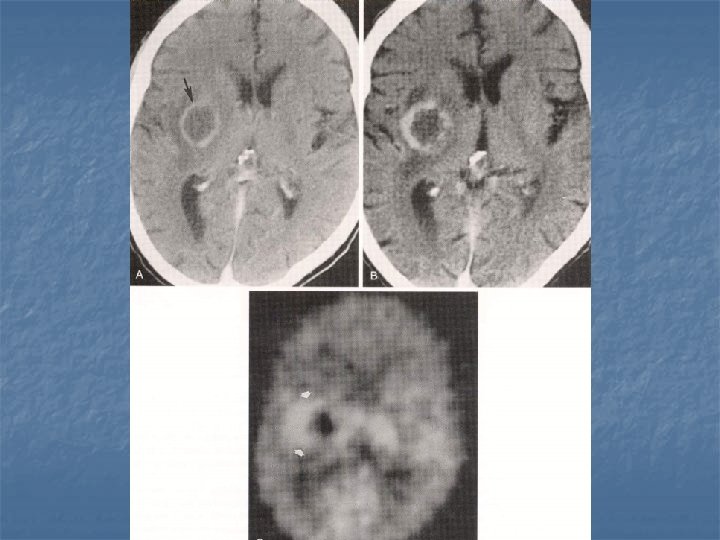

Toxoplasmosis n n n Yer kaplayan lezyonların % 60’ı % 30 olguda mevcut Kortikomedüller bileşke (? ), basal ganglion ve talamusda sık tutulum BT-MR. . . >5 lezyon, halka tarzında kontrast (+), nodüler, ödem ve kitle etkisi Erken tanı önemli. . . tedavi edilebilir 2 hafta primethamine+sulfadiazine

Biopsi n n n % 96 olguda tanı koydurucu Mortalite % 0 Majör morbidite % 2 Minör morbidite % 3 -4 Farklı çalışmalarda. . . farklı algoritmler Genel yaklaşım: Radyolojik olarak tanı konulabilen olgularda antitoxo ted. . . .